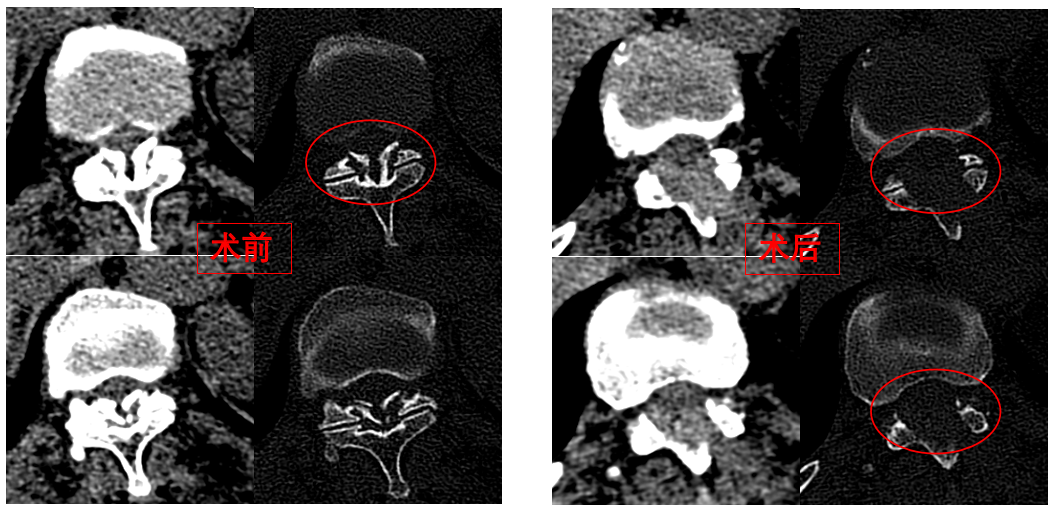

圖為卓瑪阿媽術(shù)前、術(shù)后胸椎CT照片對(duì)比。

華西醫(yī)院成辦分院骨科副主任醫(yī)師張斌接診后,憑借豐富的脊柱治療經(jīng)驗(yàn),立即安排卓瑪阿媽做了系列精密檢查,檢查結(jié)果顯示,阿媽胸椎11/12節(jié)段黃韌帶嚴(yán)重骨化,導(dǎo)致椎管顯著狹窄,脊髓受壓,確診為嚴(yán)重的“胸椎黃韌帶骨化癥”,如果不及時(shí)手術(shù)最終可能面臨癱瘓的風(fēng)險(xiǎn)。

手術(shù)歷時(shí)一個(gè)半小時(shí),骨科脊柱微創(chuàng)團(tuán)隊(duì)成功完整切除了壓迫脊髓的骨化黃韌帶,徹底解除了卓瑪阿媽的脊髓壓迫。手術(shù)過(guò)程順利,手術(shù)切口僅1厘米。